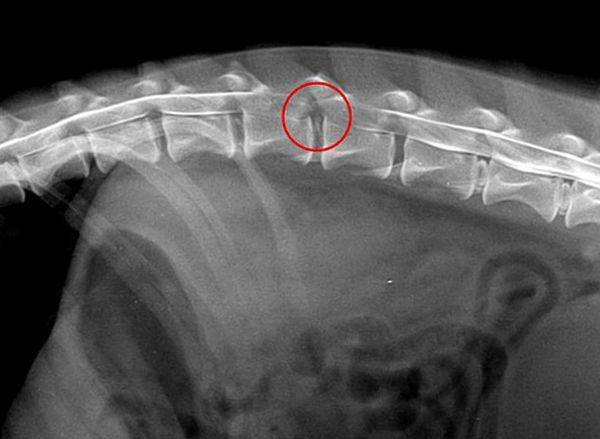

МРТ и последующее лечение у таксы

Пациент: Арчи, такса, 7 лет

Жалобы: Острая слабость задних конечностей, нарушение чувствительности, неустойчивая походка.

Диагноз: МРТ грудо-поясничного отдела позвоночника — грыжа межпозвоночного диска (IVDD) с умеренной компрессией спинного мозга. Нет признаков некроза, но требуется декомпрессия.

Что дало МРТ: МРТ точно определил уровень поражения и степень компрессии — это стало основанием для планирования микрохирургического вмешательства (гемиламинэктомии).

Результат: После операции — постепенное восстановление чувствительности и двигательной активности. На 14-е сутки Арчи сделал первые шаги. Через 8 недель — полная реабилитация.